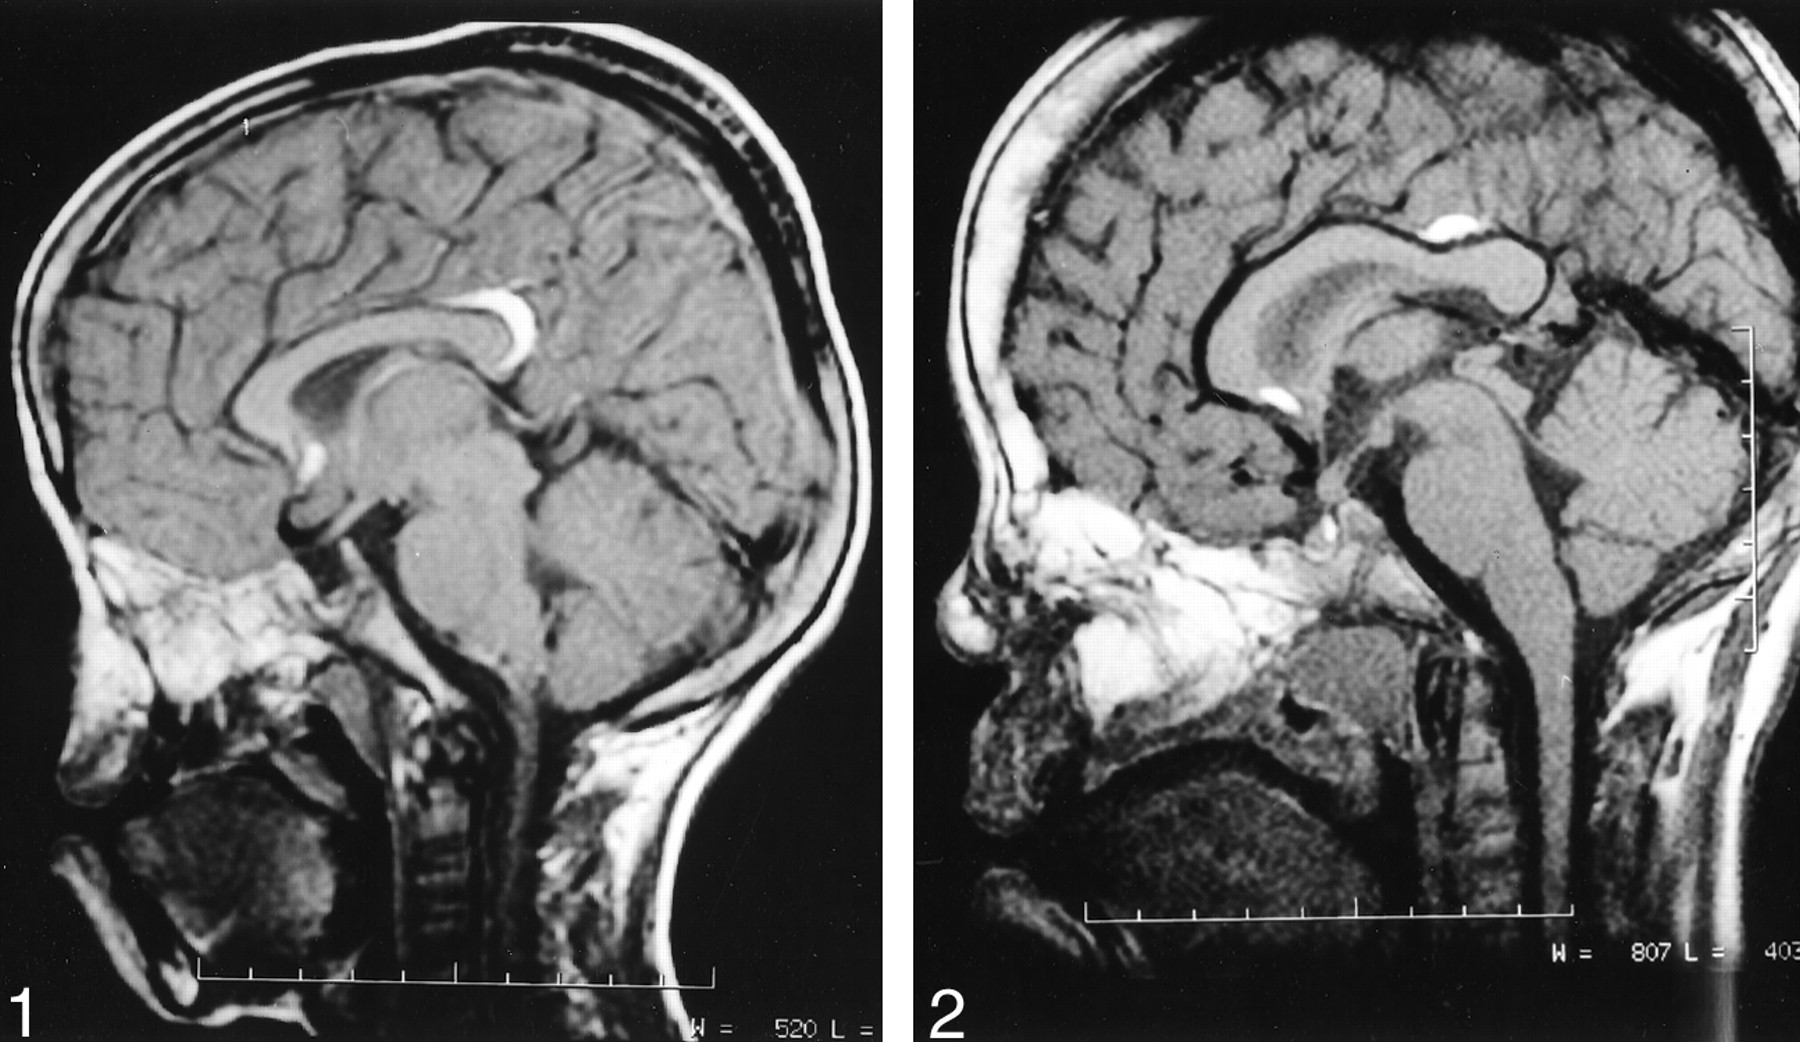

Case 2. Midsagittal T1-weighted MR image (500/20/3) of the brain shows two small curvilinear pericallosal lipomas, one in relation to the rostrum and the other in relation to the junction of body and splenium of corpus callosum. The corpus callosum is well developed. The deformity of the nose is depicted.

A 7½-year-old boy wih a cleft palate, bifid nose, absent nasal bridge, and hypertelorism presented to our hospital for surgical correction. The mother’s pregnancy and delivery were uneventful. The patient’s intelligence was normal. He had no history of seizures or headache. CT scans of the facial bones showed hypertelorism, an absent nasal septum, an anteriorly bifid nasal bone, and a depressed nasal bridge. All paranasal sinuses were absent except the anterior ethmoidal air cells. Findings from a skeletal survey were unremarkable. MR imaging revealed two pericallosal lipomas, one in relation to the rostrum and the other in relation to the junction of body and splenium of corpus callosum; these measured 0.8 and 1.5 cm in maximum diameter on the axial plane (Fig 2). The corpus callosum was well developed.